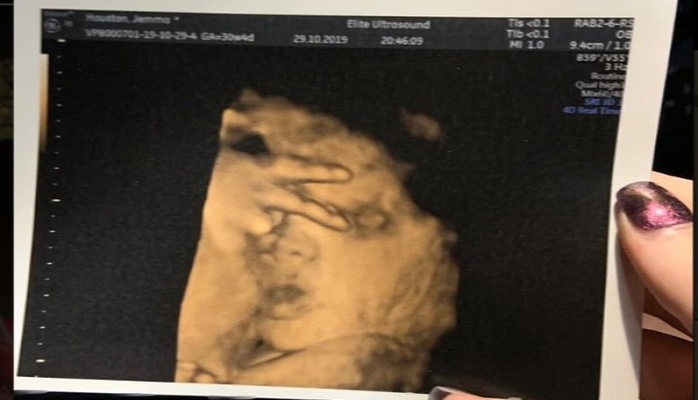

MARAQLI Doğulmamış körpə ultrasəs müayinəsində “qələbə işarəsi” göstərdi 03 noyabr 2019, 20.30 Your browser does not support the audio element. :0